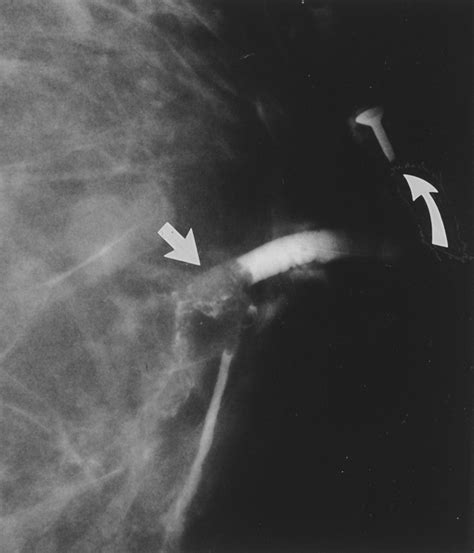

Mammogram

A mammogram is an X-ray of the breast that can help detect any abnormalities, such as tumors or cysts. This procedure is particularly important for women over the age of 40 or those with a family history of breast cancer.